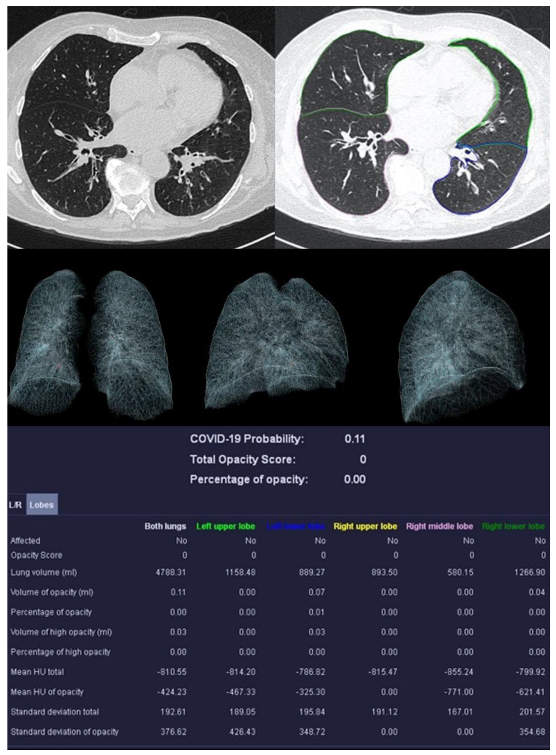

Figure 5.

Sample examination of a healthy 67-year-old patient. Only global bronchial wall thickening and mucus impactions can be seen.